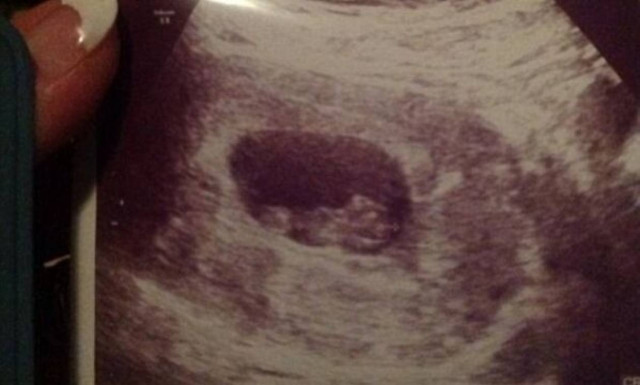

Περιμένει το τρίτο της παιδί και μας δείχνει το υπερηχογράφημά της!

Της μόδας φαίνεται ότι έχει γίνει, οι διάσημες μαμάδες να ανακοινώνουν την εγκυμοσύνη τους στα social media.